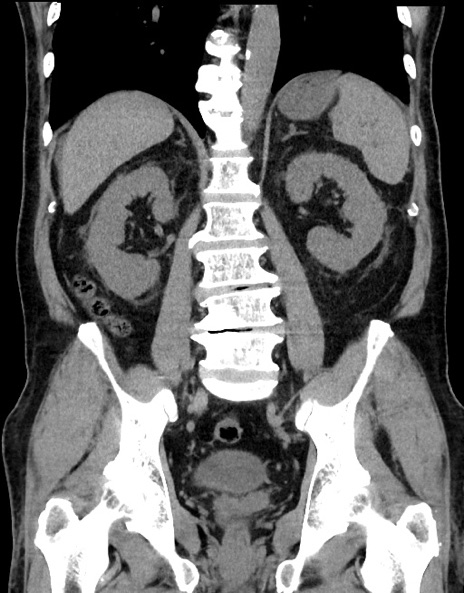

症例15(冠状断像)

【症例】70歳代男性

【主訴】腹痛

【現病歴】今朝から腹痛あり。全体的に痛い。特に左上の方。排ガスが今日はない。冷や汗が出る。

【既往歴】直腸癌術後

【身体所見】左側腹部〜上腹部に圧痛あり。腹膜刺激症状明らかなではない。軽度反跳痛。左下腹部に術後瘢痕あり。

【データ】WBC 7700、CRP 0.02